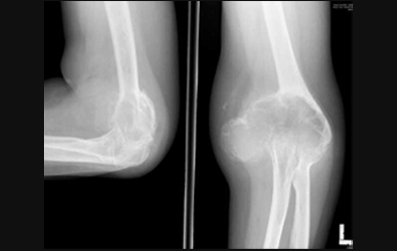

Figure 1: Preoperative radiograph showing eccentric, expansile, lytic lesion of the left medial condyle of humerus which has violated the joint. (Page 38)